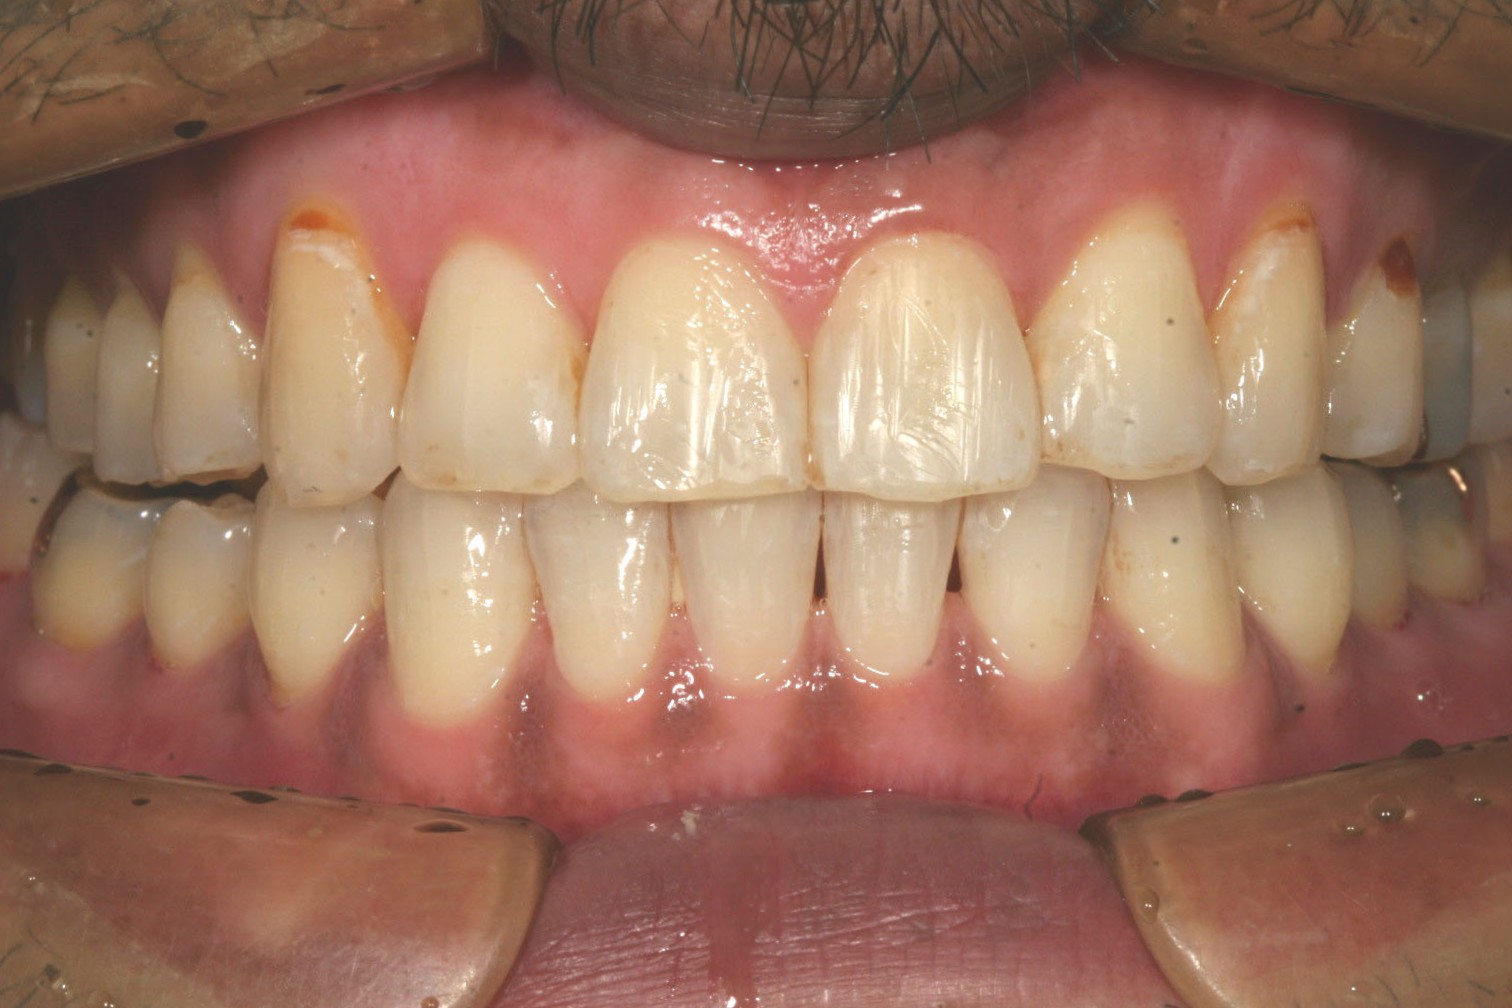

綺麗に並んでます。

側面観も綺麗になりました。

この症例は右側臼歯を後ろに順番に下げる事により犬歯が入るスぺースを確保しました。

今回は加速矯正装置PBMを使用する事により短期間で完了しました症例です。